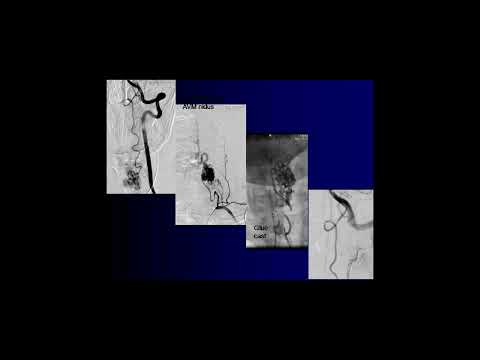

Hellow guys, Welcome to my website, and you are watching Resection of a Recurrent Intramedullary Cervical Spinal Cord Arteriovenous Malformation (AVM). and this vIdeo is uploaded by Barrow Neurological Institute at 2024-02-06T16:01:33-08:00. We are pramote this video only for entertainment and educational perpose only. So, I hop you like our website.